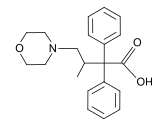

Beta-Amino Ketones

Diphenylmethylpiperazines